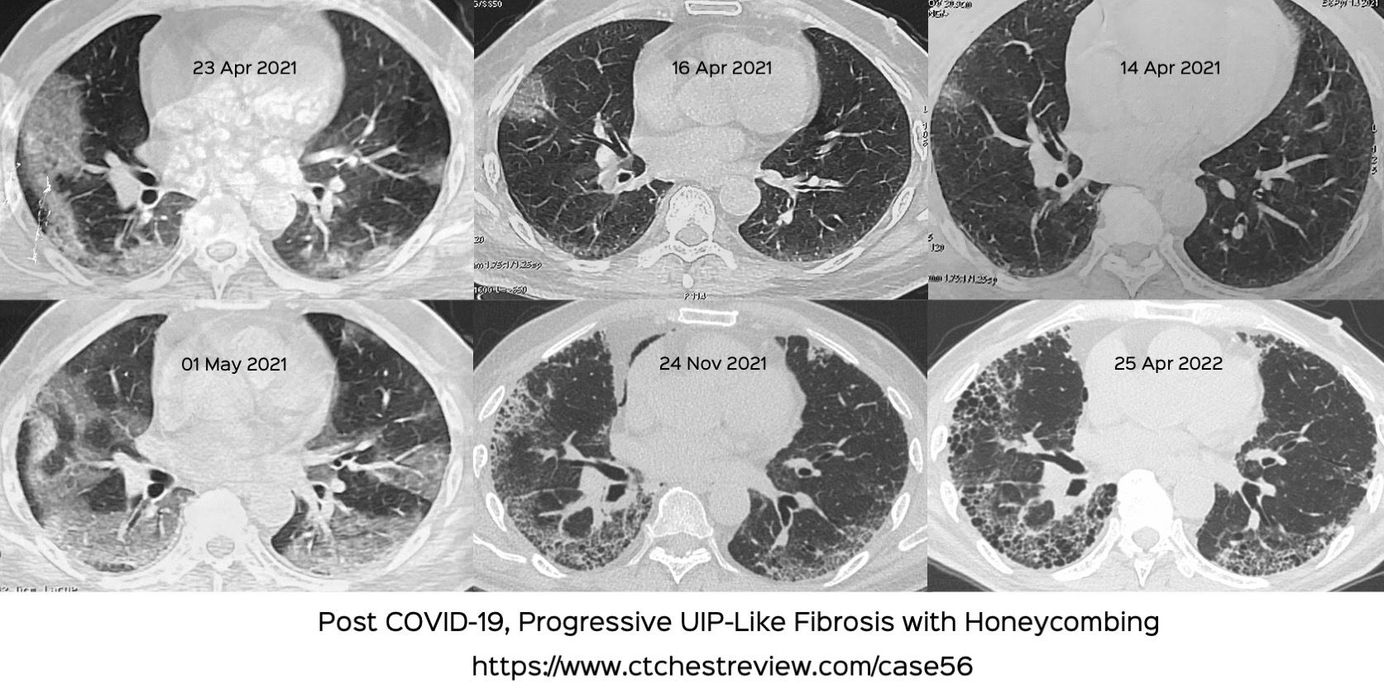

Case 56: Unusual Progressive UIP-Like Fibrosis Following COVID-19

This 66-years old non-smoker had COVID-19 in April 2021. He worsened initially and then stabilized but has since then developed a UIP-like progressive fibrosis with honeycombing, which for me, is a first.